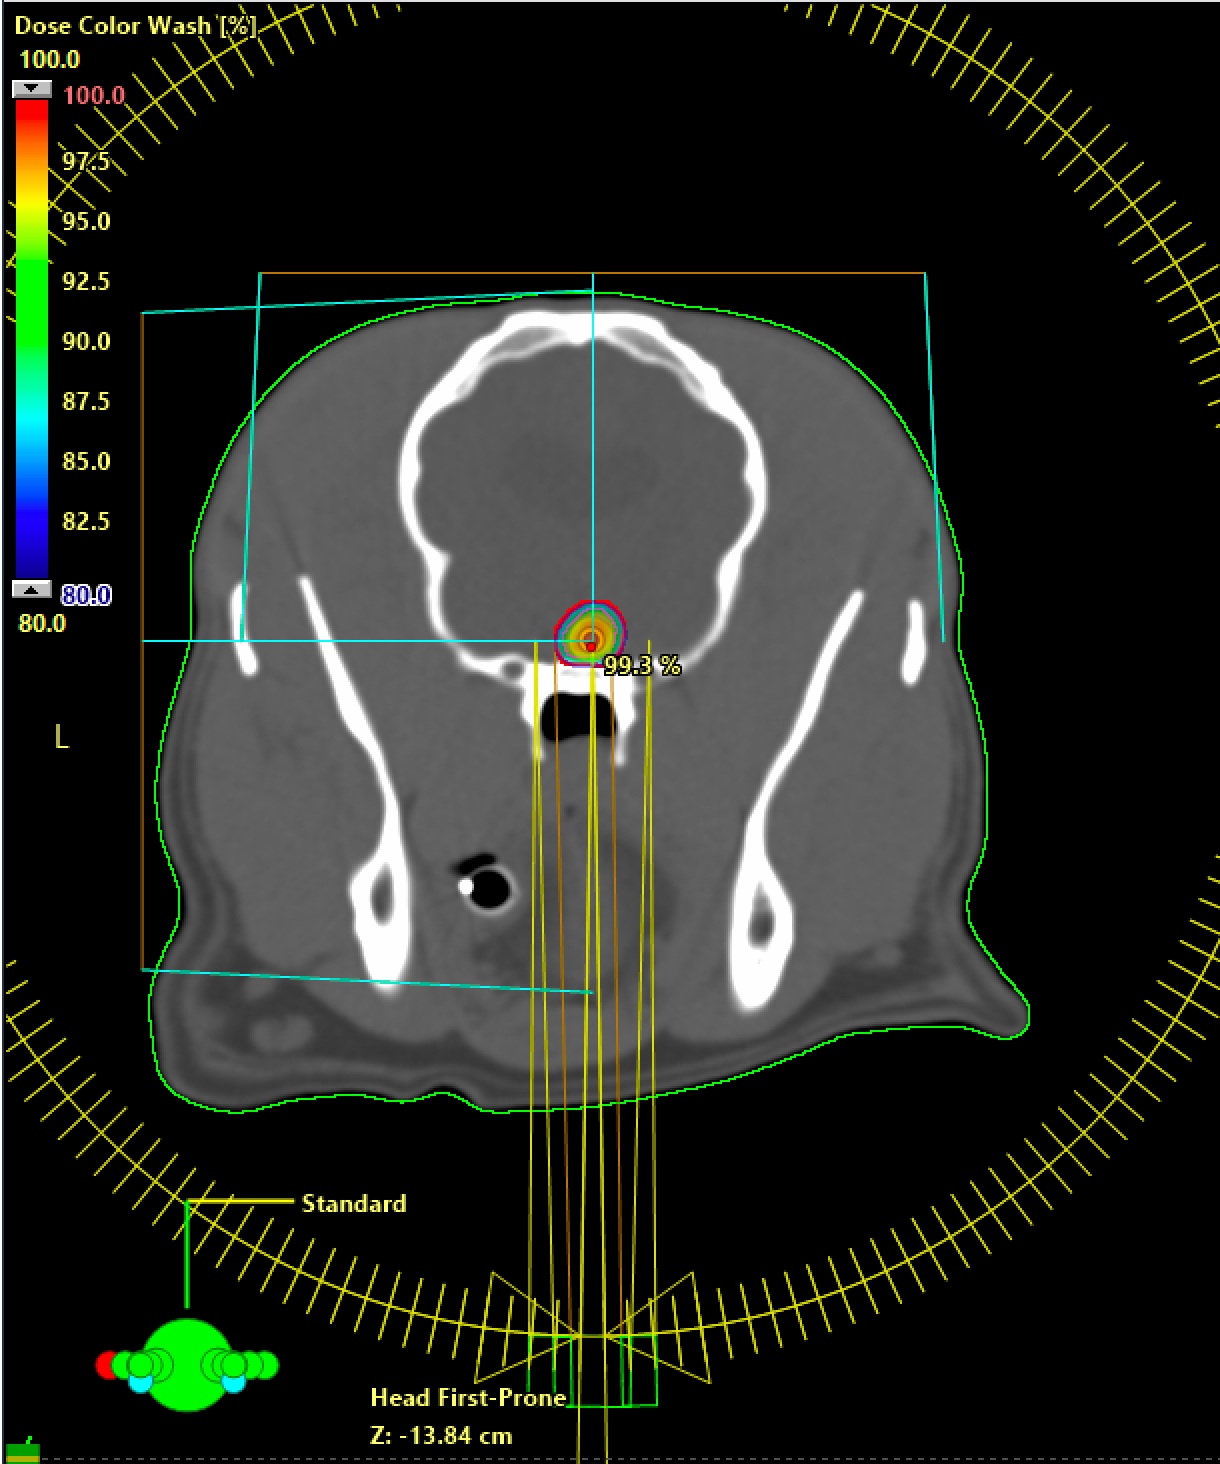

Die stereotaktische Bestrahlung ist ein hochpräzises Verfahren zur Behandlung bestimmter Tumoren. Hochdosierte Strahlen treffen gezielt das Tumorgewebe, umliegendes gesundes Gewebe wird bestmöglich geschont. Besonders geeignet ist die Methode für kleine Tumoren im Gehirn sowie an der Herzbasis, Nebenniere oder Leber. Die Behandlung erfolgt meist ambulant in 3–5 Sitzungen. Dank exakter Planung ist sie sehr wirksam und verursacht vergleichsweise wenige Nebenwirkungen.

Geräteaufnahmen vom neuen Linac in der Radio-Onkologie der Kleintierklinik am Universitären Tierspital der Vetsuisse-Fakultät der Universität Zürich